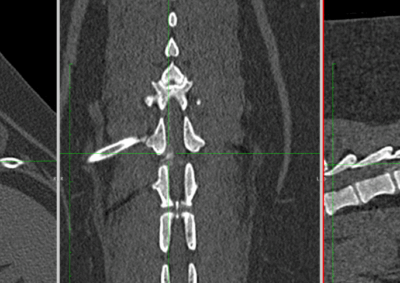

脳神経外科 注意 ボタンをクリックした先に、治療中および手術中の画像が説明で使用されている場合がございます。 そのような画像に弱い方は閲覧なさらないようお願いいたします。 脳神経外科 セメントレス環軸固定術 脳神経外科 Hemi-Laminectomy 脳神経外科 Ventral Slot 脳神経外科 椎体固定術 脳神経外科 Hemi-Laminectomy 脳神経外科 脊髄亜膜下憩室切除 脳神経外科 椎間板ヘルニア G1 脳神経外科 椎間板ヘルニア G2 脳神経外科 IVDD G5 脳神経外科 Ventral Slot 脳神経外科 Ventral Slot 脳神経外科 Ventral Slot 123456> 症例カテゴリー 放射線治療整形外科軟部組織外科脳神経外科内科腫瘍外科救急・集中治療リハビリテーション科腫瘍内科内視鏡科脳神経科呼吸器外科中医・漢方猫の腎移植循環器科電気化学療法